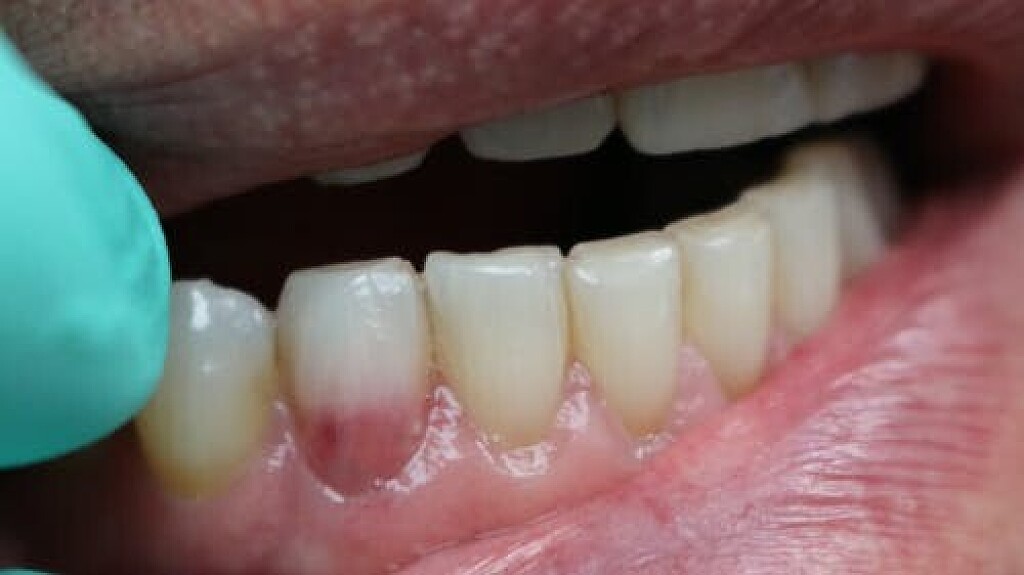

An internal resorption pink spot was historically referred to as the “pink tooth of Mummery,” named for the anatomist who described the condition. Like an ECR lesion, in this type of resorption, patients are typically asymptomatic, and the lesion is only noted either by its pink color that patients may notice prior to their visit or from routine radiographs.

In order for this type of resorption to occur, some type of damage had to take place inside the predentin layer, with inflammation present. Predisposing factors for this type of resorption include caries, trauma, restorative procedures, and heat. Vital pulp tissue is needed for this type of resorptive process to continue.

If the lesion becomes significant in size, necrosis of the pulp usually occurs, at which point the patient will begin to have typical pulpitis-related symptoms. Since the vascular tissue becomes necrotic, the tooth’s color may appear darker or gray with discoloration. Root canal therapy will resolve this type of resorptive process. As long as the process has not resorbed a significant portion of the tooth, prognosis is favorable. Repairs can be made with bioceramics, even in situations where the lesion has perforated to the external surface.